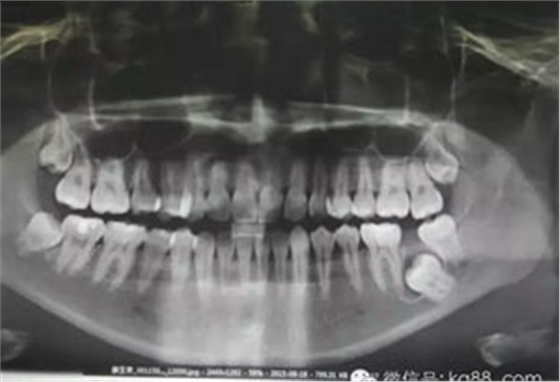

圖1.術(shù)前患者的全景片影像檢查情況:37未萌出,牙冠周圍有囊性陰影,牙根接近下頜骨皮質(zhì)骨邊緣。

1.jpg